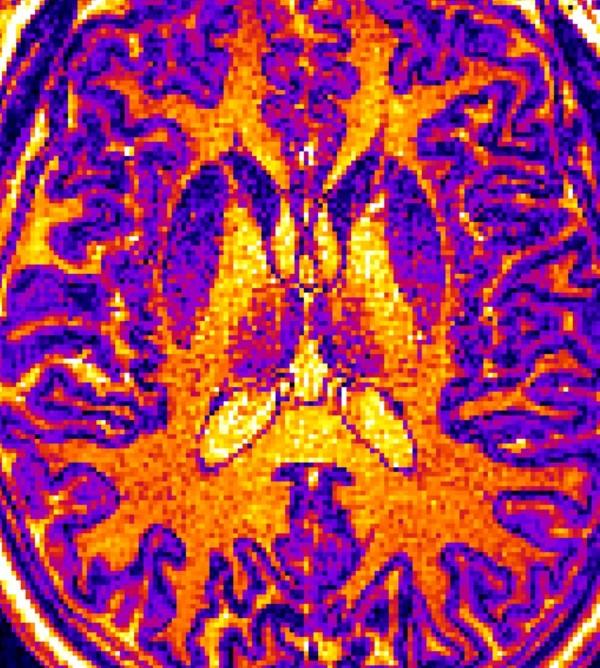

image: MRI images like this one were screened by a machine learning computer algorithm designed by a research team at the University of Tokyo. The algorithm learned to identify the brains of nonpatients, patients diagnosed with autism, and patients diagnosed with schizophrenia based on subtle but statistically important differences in the thickness, volume, or surface area of certain regions of the brain. This tool may help make future mental health diagnosis more objective rather than relying solely on statements from patients and their families.

The algorithm used in this study learned to associate different psychiatric diagnoses with variations in the thickness, surface area or volume of areas of the brain in MRI images. It is not yet known why any physical difference in the brain is often found with a specific mental health condition.

The research team also noted that the thickness of the cerebral cortex, the top 1.5 to 5 centimeters of the brain, was the most useful feature for correctly distinguishing between individuals with autism spectrum disorder, schizophrenia and typical individuals. This unravels an important aspect of the role thickness of the cortex plays in distinguishing between different psychiatric disorders and may direct future studies to understand the causes of mental illness.